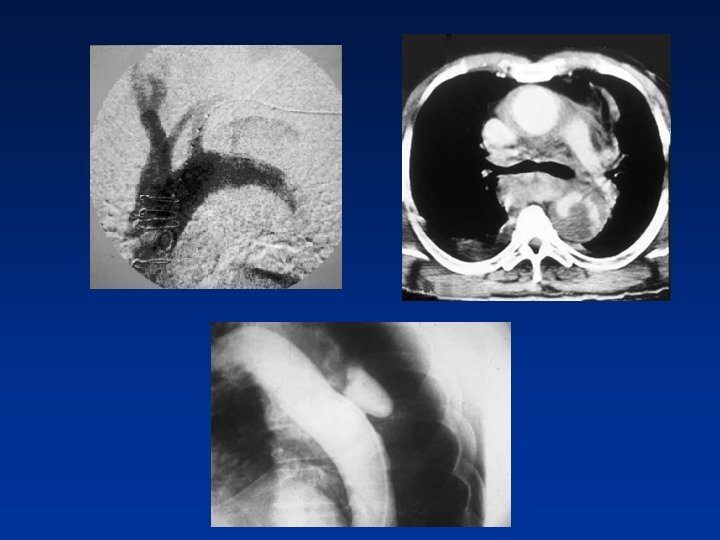

Doenças da aorta torácica • Dissecção aguda da aorta(tipo B) • Dissecção crônica da aorta • Hematoma intramural • Aneurisma verdadeiro • Pseudoaneurisma

Tratamento Endovascular

Endoprótese Torácica E. Saadi/2008

Aneurisma Aorta Torácica e Dissecção de Aorta • • • • Cirurgia dealto altíssimo Cirurgia de risco Mortalidade 20%% Mortalidade 55 - -20 Morbidade(complicações): -- paraplegia: : 55 -- 20 20% % -- AVC 10 a 20 dias de hospitalização, -5 Amputação de M. Inferiores a 7 dias em UTI 10 20 CEC dias de hospitalização, 5 Usoade a 7 dias em UTI Obrigatório o uso de CEC